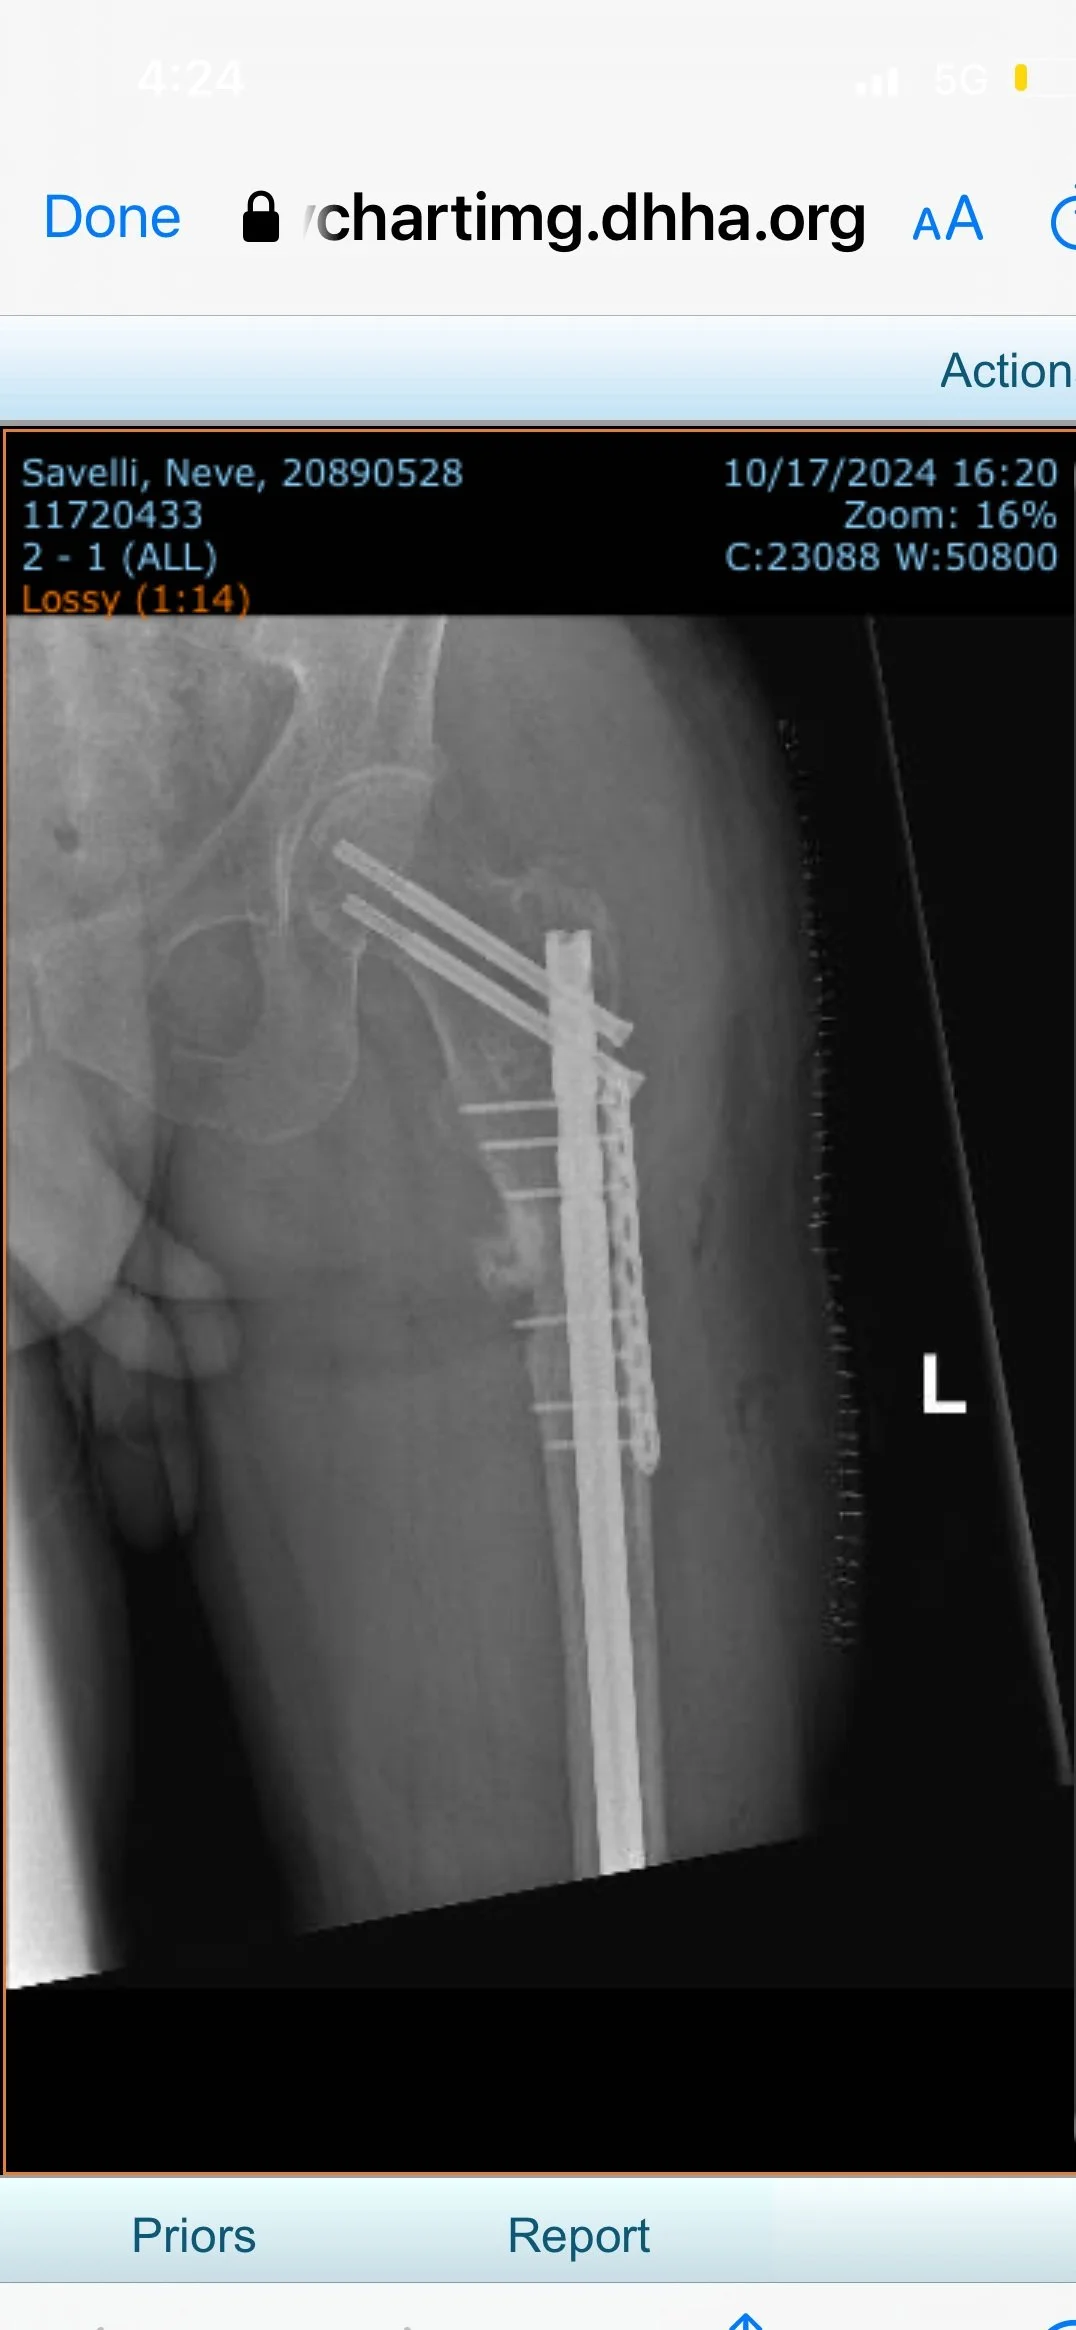

Revision surgery for failed fracture fixation